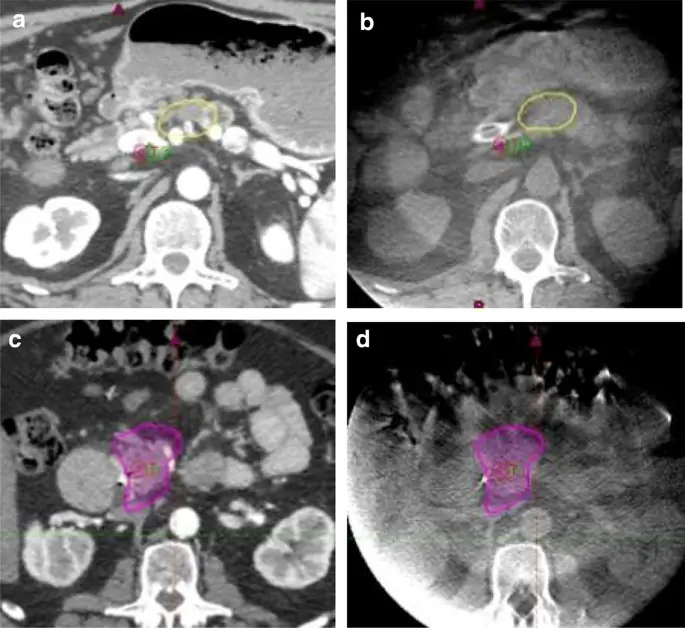

Адаптивное планирование используется как решение для неслучайного движения желудочно-кишечного тракта. Мы оцениваем ежедневное движение органа, используя ежедневный CBCT, спроецировав линию изодозной максимальной дозы (Таблица 3) как структуру наших ежедневных CBCT (Рис. 2). Положение желудка, двенадцатиперстной кишки, тощей кишки и толстой кишки относительно прогнозируемых IDL легко заметить. Адаптивное планирование запускается, когда одна и та же часть органа пересекает линию изодозы более трети времени. Такое избирательное адаптивное планирование было подтверждено опытом последних 10 лет. Такой подход минимизирует количество адаптивных планов и повышает операционную эффективность. Наиболее распространенные причины адаптивного планирования связаны с газом в желудке, неслучайным движением тощей кишки и газом в луковице двенадцатиперстной кишки. Когда необходим адаптивный план, CBCT, слитый с CT моделирования, может использоваться для изменения контуров OAR на CT моделирования и перепланировки без повторения моделирования.

CBCT используются для проверки целевого положения, а также ежедневных изменений в положении соседнего просвета желудочно-кишечного тракта. Симуляционные КТ двух пациентов, отображающие критическую максимальную дозу для желудка (желтый) (а) и тонкой кишки (пурпурный) (в). Соответствующие изображения DIBH CBCT с одинаковыми линиями изодозы (b и d) показаны справа. На положение желудка может повлиять наполнение пищей и воздухом (а и б), в то время как двенадцатиперстная кишка очень воспроизводима (в и г)